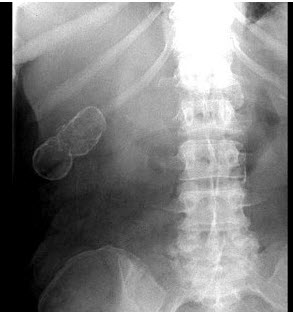

59、单项选择题

女,39岁,右上腹部隐痛,有慢性胆囊炎史,曾经做过口服胆囊造影,胆囊显影差,X线检查如图,最可能的诊断是()

A.急性胆囊炎

B.慢性胆囊炎

C.胆囊结石

D.瓷样胆囊

E.胆囊结核